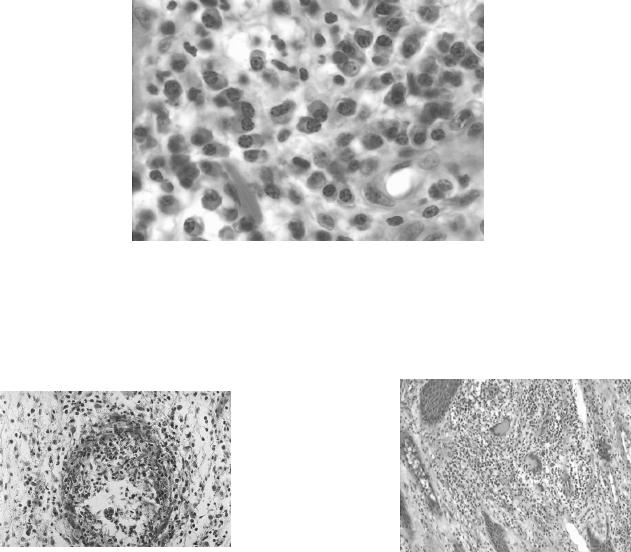

Figura 16: Granuloma micótico misto organizado polar com alta intensidade dos elementos

celulares (setas) e fungos (seta azul), em biópsia de lesão elevada. HE 20x.........33

Figura 17: Granuloma micótico misto organizado polar com baixa intensidade dos

elementos celulares e fungos (seta), em biópsia de lesão plana. HE 40x...............34

Figura 18: Imagem de GMMO polar de baixa intensidade em biópsia lesão plana. HE 40x....34

Figura 19: Imagem de gigantócito contendo célula fúngica deteriorada em GMMO polar

de baixa intensidade em biópsia de lesão plana. HE 100x no original...................34

Figura 20: Imagem de GMMO polar de alta intensidade em biópsia de lesão elevada

mostrando eosinófilos, plasmócitos, linfócitos, macrófagos, células gigantes,

neutrófilos e corpos escleróticos. HE 40x no original.............................................34

Figura 21: Imagem de GMMO polar de alta intensidade em biópsia de lesão elevada

mostrando infiltrado linfo-plasmocitário, com macrófagos,presente na

periferia dos granulomas. HE 40x no original.........................................................35

Figura 22: GMMO polar de baixa intensidade em biópsia de lesão plana.

HE 20x no aumento original....................................................................................35

Figura 23: GMMO polar de alta intensidade em biópsia de lesão elevada

com áreas de fibrose e vasculite. HE 10x...............................................................35

Figura 16: Granuloma micótico misto organizado polar com alta intensidade

dos elementos celulares (setas) e fungos (seta azul), em biópsia de lesão elevada. HE 20x.

Figura 17: Granuloma micótico misto organizado polar com baixa intensidade

dos elementos celulares e fungos (seta), em biópsia de lesão plana. HE 40x.

Figura 18: Imagem de GMMO polar de baixa intensidade Figura 19: Imagem de gigantócito contendo célula fúngica

em biópsia lesão plana. HE 40x. deteriorada em GMMO polar de baixa intensidade em

biópsia de lesão plana. HE 100x no original.

Figura 20: Imagem de GMMO polar de alta intensidade em biópsia de lesão elevada mostrando

eosinófilos, plasmócitos, linfócitos, macrófagos, células gigantes, neutrófilos e corpos escleróticos. HE 40x no original.

Figura 21: Imagem de GMMO polar de alta intensidade em biópsia de lesão elevada mostrando

infiltrado linfo-plasmocitário, com macrófagos, presente na periferia dos granulomas. HE 40x no original.

Figura 22: GMMO polar de baixa intensidade em biópsia de lesão plana. Figura 23: GMMO polar de alta intensidade em biópsia

HE 20x no aumento original. de lesão elevada com áreas de fibrose e vasculite. HE 10x.